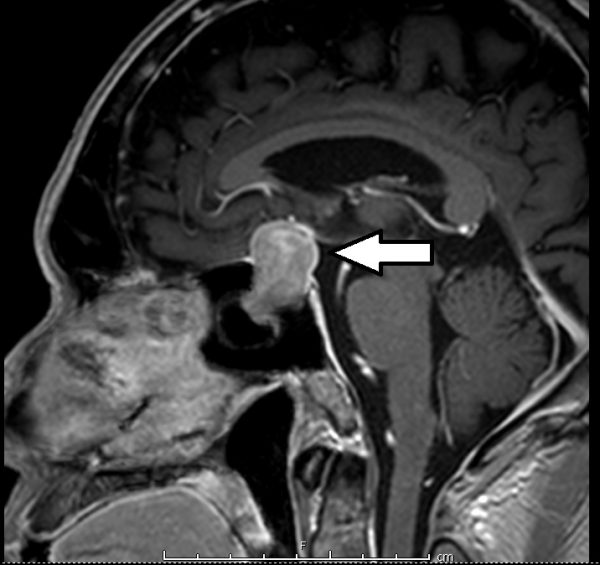

这颗肿瘤体积是2x2x2.5公分,和细小的脑下垂体比较,显得十分巨大,从磁力共振扫描照片上看到,它刚好长在视神经线的交叉处下方,往上推挤视交叉,造成双眼的外侧上端视野丧失。